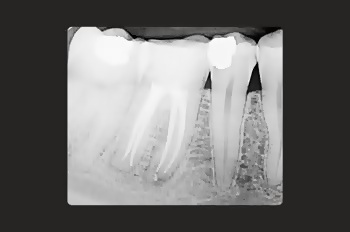

At Moltons Dental, we are committed to delivering the highest precision and care by utilising the Zeiss Extaro microscope for root canal treatments and restorative procedures.

This cutting-edge technology allows us to perform procedures with excellent precision and detail.

The Zeiss Extaro microscope enhances visibility, accuracy, and treatment outcomes, giving our patients the most reliable and predictable experience.